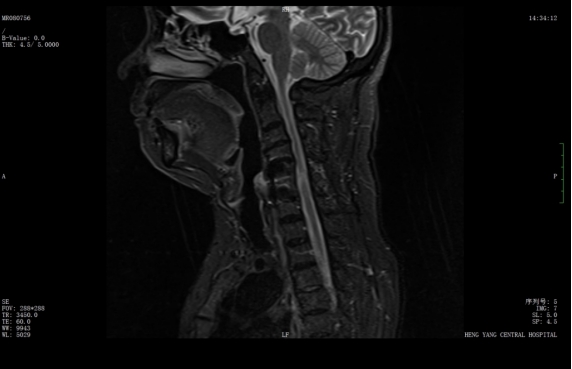

該患者此前因膽囊結(jié)石祁東縣人民醫(yī)院治療,來自衡陽市中心醫(yī)院駐該院副院長李攀峰為其主刀進(jìn)行手術(shù),術(shù)后患者恢復(fù)良好。后因突發(fā)四肢癱瘓、生活無法自理,為尋求進(jìn)一步治療,經(jīng)醫(yī)聯(lián)體通道轉(zhuǎn)入衡陽市中心醫(yī)院。脊柱外科錢軍博士團(tuán)隊(duì)接診后,迅速組織詳細(xì)問診、體格檢查及系統(tǒng)術(shù)前評估。查體顯示患者四肢關(guān)鍵肌肌力僅I級,感覺功能明顯減退,結(jié)合影像學(xué)結(jié)果,診斷為頸脊髓損傷伴不全癱,有明確手術(shù)指征。

考慮到患者20年前曾有頸脊髓外傷史,并于外院行頸椎前路手術(shù),此次手術(shù)區(qū)域存在嚴(yán)重瘢痕粘連,極大增加了手術(shù)難度與風(fēng)險(xiǎn)。錢軍博士團(tuán)隊(duì)迅速啟動多學(xué)科會診,為患者制定個性化手術(shù)方案,最終決定施行頸椎后路手術(shù),擴(kuò)大椎管容積,徹底解除神經(jīng)壓迫問題。

術(shù)前核磁共振提示:頸椎椎管狹窄、頸脊髓信號改變